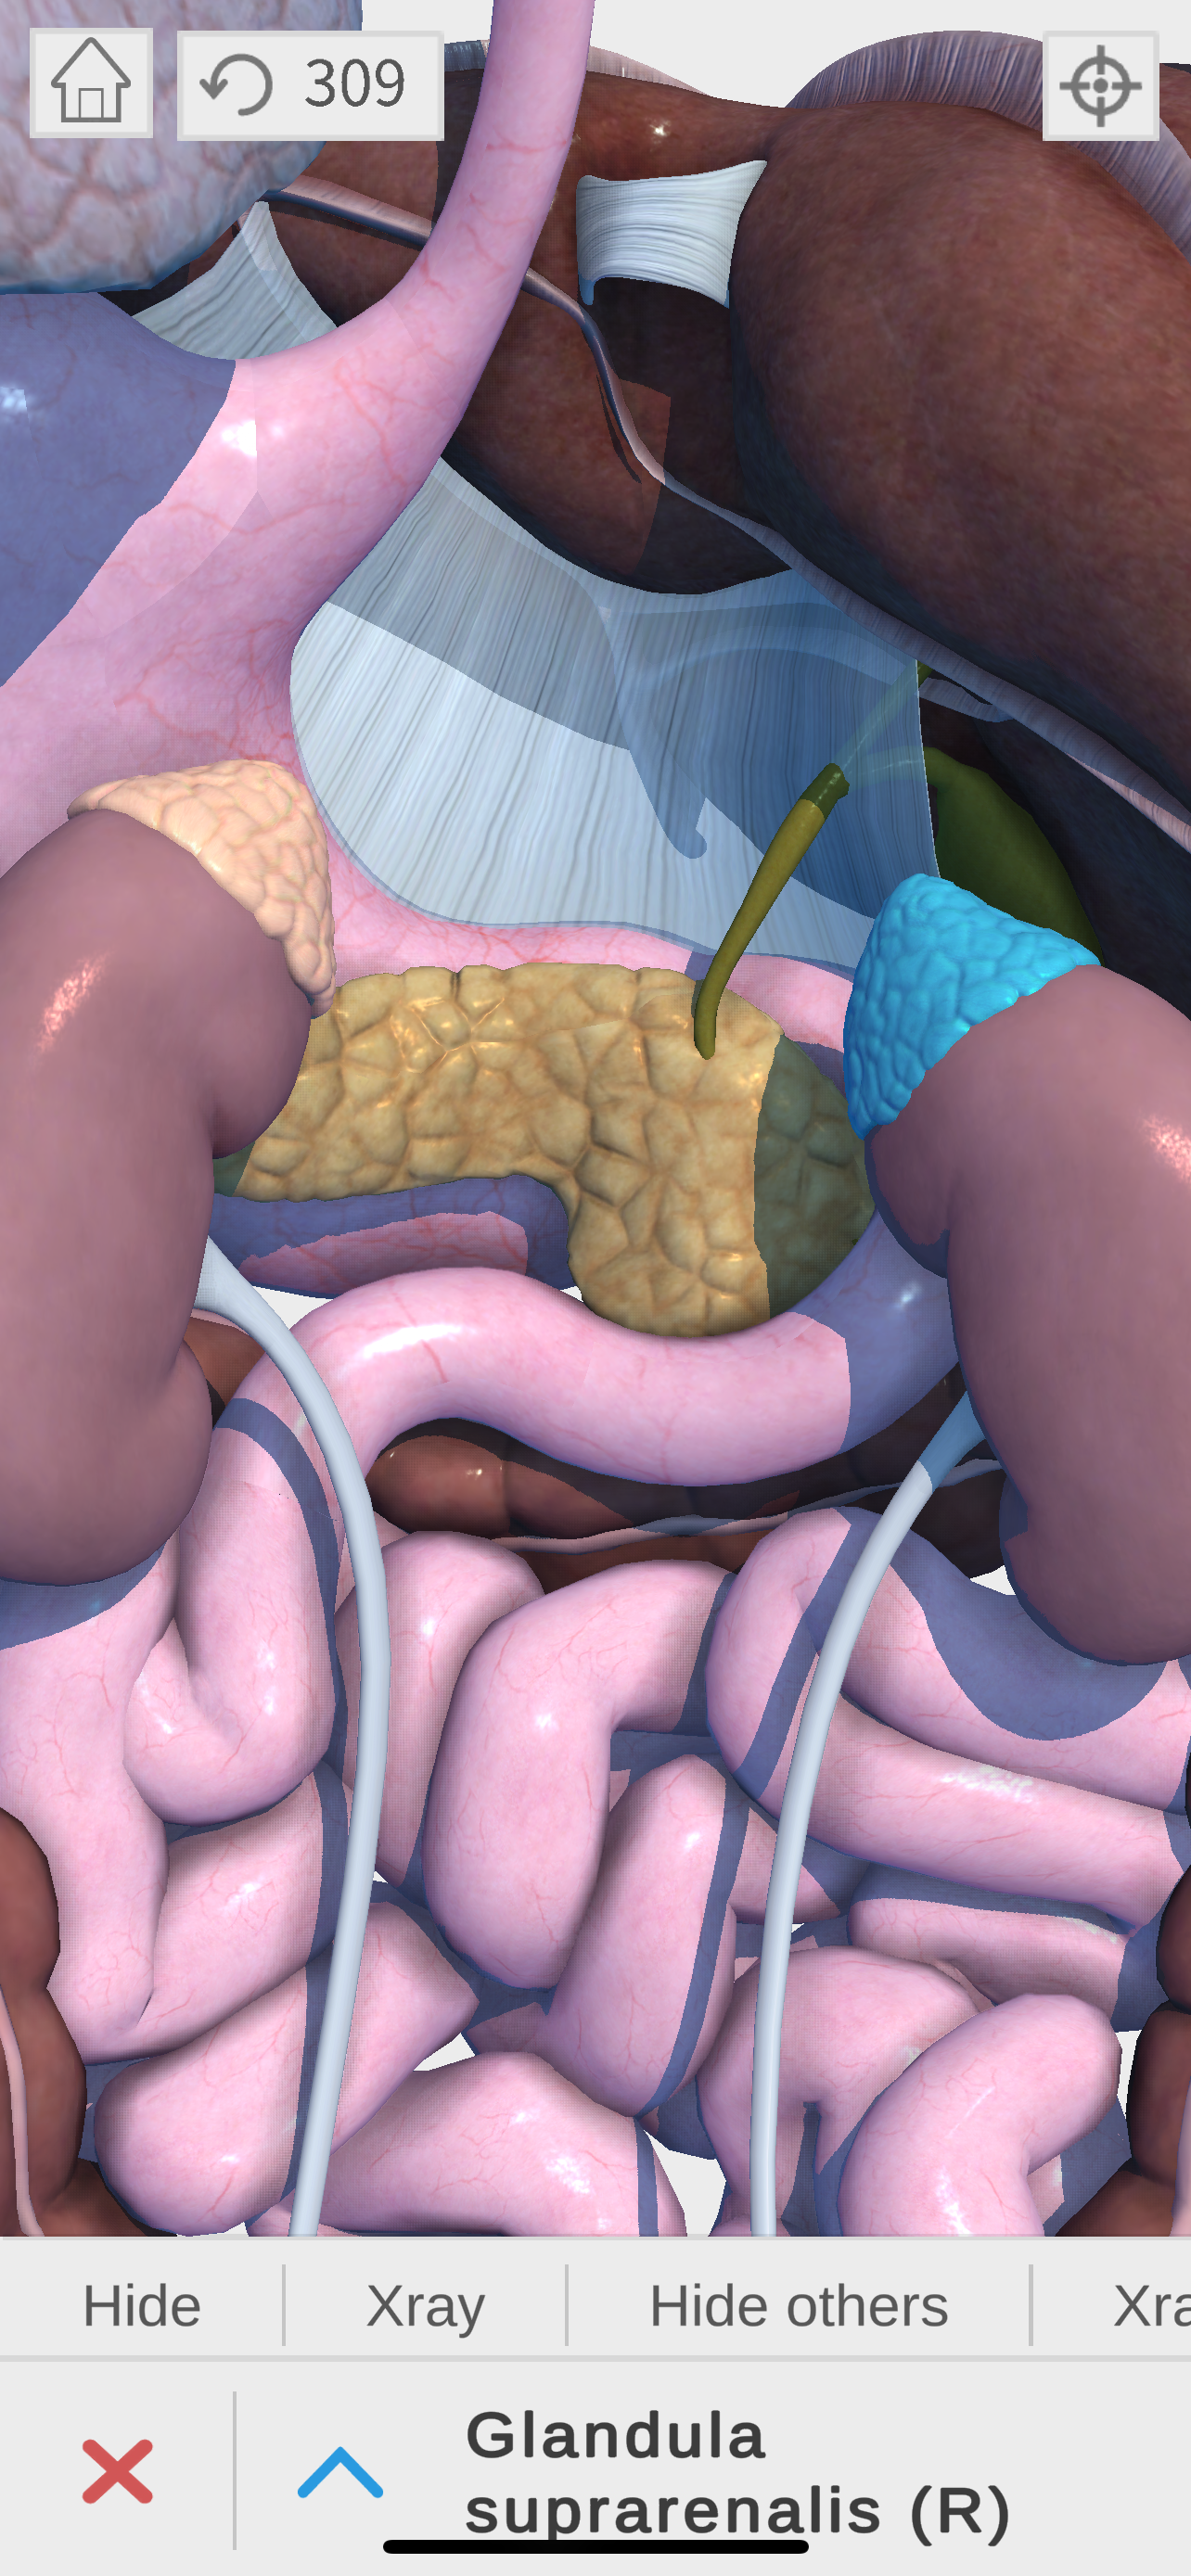

Complete and easy-to-use virtual guide for learning, understanding, and visualizing the complexities of human anatomy in 3D. Includes information and images for each anatomical system and part, multiple options to interact with the 3D anatomy models (hiding, fading, etc), and much more.

We believe that learning by interaction is the best and easiest way to study human anatomy.

- highly detailed

- zoom, pan, and rotate in real time

- show and hide layers

- see details for each body part

- Endocrine